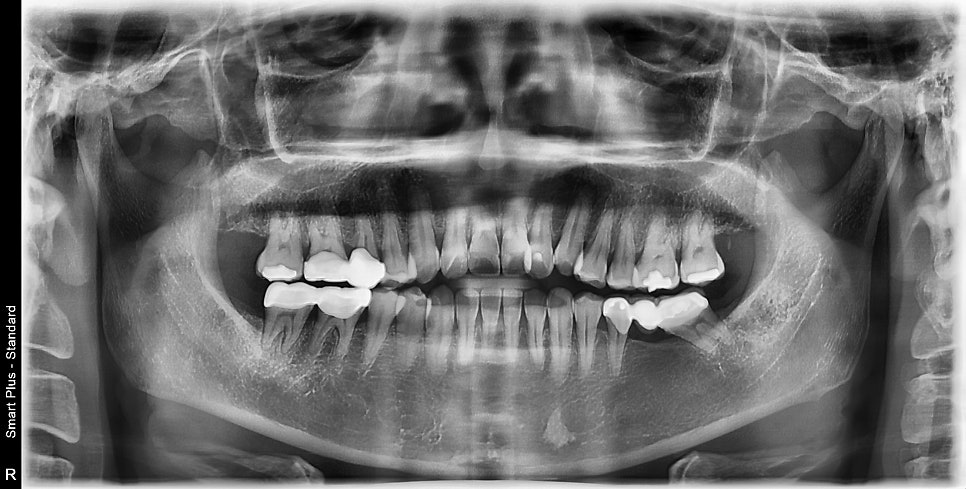

엑스레이에서 보듯이

최후방 치아가 깨지고 주변 치아뿌리인대가

비후 되어있었습니다.